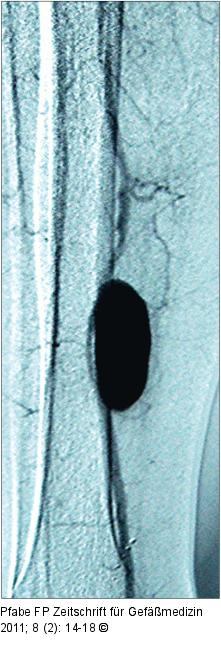

Abbildung 11: Insuffizienz der distalen Bypassanastomose Aneurysma spurium der A. tibialis posterior nach Fogarty-Manöver. Insuffizienz der distalen Bypassanastomose mit massiver Einblutung. |

Abbildung 11: Insuffizienz der distalen Bypassanastomose

Aneurysma spurium der A. tibialis posterior nach Fogarty-Manöver. Insuffizienz der distalen Bypassanastomose mit massiver Einblutung. |